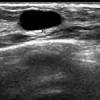

A pet scan will help detect cancer and show how far it has spread. Ct scans can produce false negatives and false positives. In some instances, cancers may not show on the scan. Ultrasound may also be used to locate the position of a tumor in order to guide the doctor during a biopsy or aspiration procedure. After spending a day at the sydney breast clinic, her worst fears were confirmed.

Ultrasound may also be used to locate the position of a tumor in order to guide the doctor during a biopsy or aspiration procedure. Sandy,i asked my onc.he says ct's can pick up breast cancer depending part on location.i guess it's like real estate,location,location,location,lol.but seriously theradiologist who read my lung ct in november wrote in his report specifically there was no evidence of breast cancer.i guess due to them watching a lymph gland for 2 years on my rt breast.it was fine in mammogram in october so i am now back to yearly,thank god,andib She spent months, getting more surgery, chemotherapy and radiation and 8 months later and she was cleared for work. Ct scans can help doctors: A pet/ct scan is a newer technology used to create images of the body's cells as they work. These scans expose you to more. Doctors use a computed tomography (ct) scan, also called a cat scan, to find cancer. Results from a recent retrospective study conducted by memorial sloan kettering cancer center investigators suggest that pet/ct scanning might offer the most efficient and effective detection of newly diagnosed breast cancer that has spread to the bone. Are they as reliable in detecting breast cancer as a regular mammogram? Benefits of a ct scan. It is common for patients to receive a diagnosis for cancer of unknown primary. This test is most often used to look at the chest and/or belly (abdomen) to see if breast cancer has spread to other organs. Should you get a ct scan to detect possible tumors?